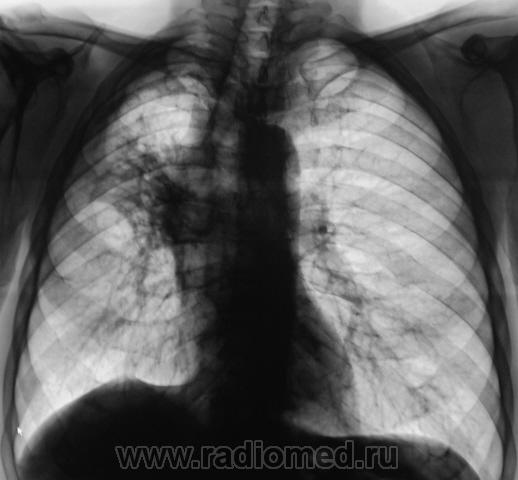

Произведено дообследование.

ИзображениеИзображениеИзображение

Пациент направлен на консультацию к фтизиатру. Произведено общеклиническое дообследование, пациент госпитализирован в туб. большицу.